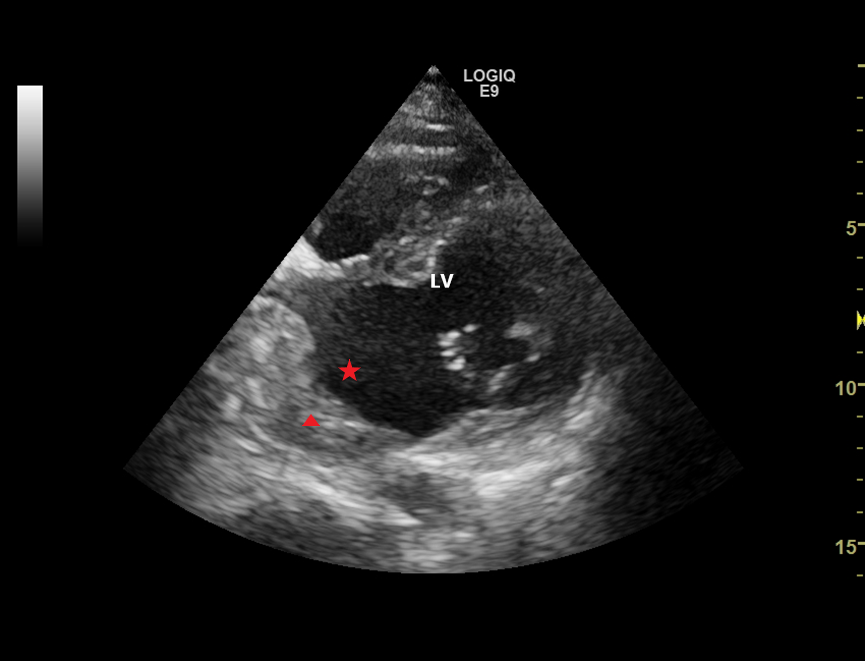

左房前后径:38mm , EF:53% , FS:28% , SV:74ml 。左室短轴切面,可见后间隔基底段、左室下壁基底段心肌变薄,运动及增厚率减低,局限性向外膨出呈瘤样改变,瘤体范围约 58x57mm ,瘤颈宽约 56mm ,瘤体内部可见范围约 51x20mm 的等回声团块。CDFI:瘤体内血流速度缓慢。

左室下壁真性室壁瘤伴附壁血栓形成。

本例患者是一例较大的左室下壁室壁瘤,但患者没有胸痛的病史,在标准的左室长轴切面和心尖四腔心切面,并没有显示出室壁瘤,而在左室短轴切面,和不规则的心尖切面可以显示,因此,我们在工作中,一定要多切面扫查,以防漏诊。